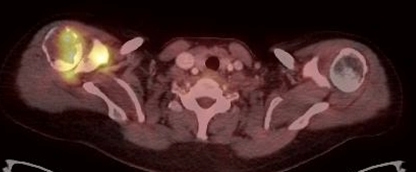

Se obtuvo un estudio PET-CT de cuerpo entero 50 minutos después de la administración IV de 7,8 mCi de 18F-FDG; el componente CT se realizó con medio de contraste yodado (equipo Siemens mCT). El estudio demostró lesiones osteolíticas hipermetabólicas en la cabeza humeral derecha, cavidad glenoidea y partes blandas adyacentes con valor de captación estandarizado (SUVmax) = 9,2. También mostró múltiples lesiones osteolíticas e hipermetabólicas vertebrales y costales con masa de partes blandas hipermetabólica que infiltra la musculatura dorso-lumbar y femoral. Se observó aumento del metabolismo en el plano cutáneo de axila izquierda y vulva, en correspondencia con lesiones ulceradas, así como también un nódulo hipofisario de 14 mm, hipermetabólico, con SUVmax = 22,5 (figs. 1,2 y 3 A). Los pulmones, mediastino, hígado, bazo, glándulas suprarrenales y páncreas no presentaron alteraciones del metabolismo ni tampoco se identificaron adenopatías hipercaptantes.

Un 18FDG PET-CT de control post-terapia (figs. 1,2 y3 B) mostró significativa disminución metabólica de la lesión hipofisaria, del componente de partes blandas en hombro derecho y de las lesiones en columna, con persistencia sin cambios de las lesiones osteolíticas en TAC. Dada la respuesta parcial a la terapia, se inicia segundo curso de vinblastina semanal 6 mg/m2 por 6 semanas y prednisona 40 mg/m2 por 3 días a la semana.